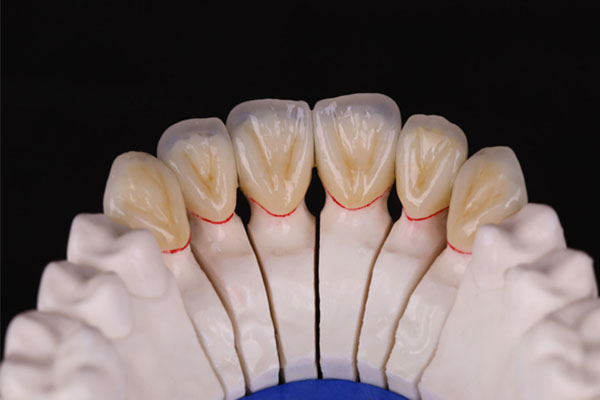

牙齿缺失不仅会影响咀嚼功能,还可能导致邻近牙齿倾斜、对颌牙齿伸长,从而引发牙齿疼痛。如果你有牙齿缺失的情况,中老年口腔的种植牙和活动义齿修复方案能够快速恢复你的牙齿功能,避免因牙齿缺失引发的疼痛问题。我们的修复技术不仅高效,还能让你的牙齿看起来更加自然。